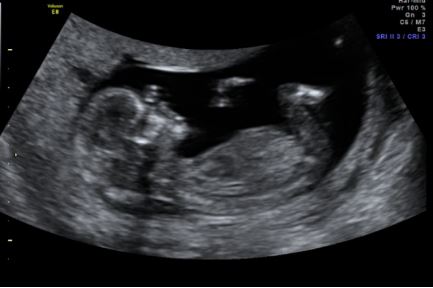

Finally had my 12 week scan today. By our dates we were 12w4d but bubs was measuring 13w2d. So happy because all the tests came back super low risk so pretty over the moon right now :) That said still curious about the gender...

I don't know whether I saw a nub or not. We did try to sway for blue, but I am quite keen on the idea of having 2 little girls as well so whatever the guess I'm keen to hear it. I'm also interested to know if you can tell anything from the skull shape. I have so many pictures but I don't think I can see a proper nub shot in any of them - that said I've never been very good at picking with other people so no surprise I can't pick my own lol.